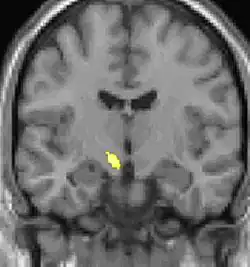

Positron emission tomography (PET) shows brain areas being activated during pain.

Voxel-based morphometry shows brain area structural differences.

Positron emission tomography (PET) scans indicate the brain areas which are activated during attack only, compared to pain free periods. These pictures show brain areas that are active during pain in yellow/orange color (called "pain matrix"). The area in the center (in all three views) is activated only during cluster headaches. The bottom row voxel-based morphometry shows structural brain differences between individuals with and without CH; only a portion of the hypothalamus is different.[36]